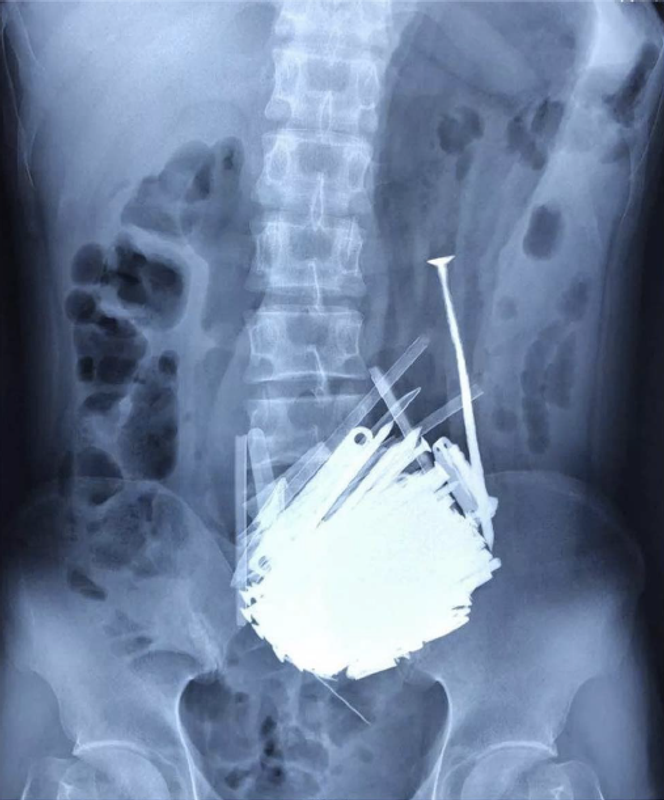

La radiographie montre la présence de nombreux objets métalliques dans l’estomac. Lors de l’endoscopie, les médecins observent de nombreux corps étrangers dans la partie inférieure de l’estomac, responsables d’une obstruction de la vidange gastrique.

Près de trois kilos d’objets métalliques retirés de l’estomac

Le patient est opéré. L’intervention consiste à réaliser une incision longitudinale de dix centimètres sur l’estomac, dont la cavité est remplie de nombreux objets métalliques. Au total, 452 vis, clous, écrous, clés, pierres et autres fragments de métal, pour un poids de 2,9 kg, sont extraits de l’estomac.